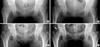

Fig. 5

Serial coronal 3D-CT images taken during follow-up are shown. Coronal CT image of a healthy young woman (control) shows well-oriented vertical primary compression trabeculae with normal bone density in both femoral heads. Image obtained at 4 weeks postpartum (4 w) shows reduced bone density in both proximal femurs, and a loss of thickness and continuation of vertical primary compression trabeculae. Area of irregular spotty increased bone density (arrowhead) is observed in the left femoral head immediately below the subchondral bone plate. Breakages of the subchondral bone plate (short arrows) and a sclerotic line (long arrow) obliquely crossing vertical primary compression trabeculae are observed in the right femoral head. Image taken at 11 weeks postpartum (11 w) shows a marked increase in trabecular density in both femoral heads. Area of irregular spotty bone density (arrowhead) is also observed in the right femoral head. Image taken at 20 weeks postpartum (20 w) shows almost normal appearing vertical trabeculae in both femoral heads. The irregular spotty bone density decreased. Image taken at one year postpartum (1 y) shows normalized vertical trabeculae in both femoral heads. The irregular spotty bone density has decreased further at this stage.